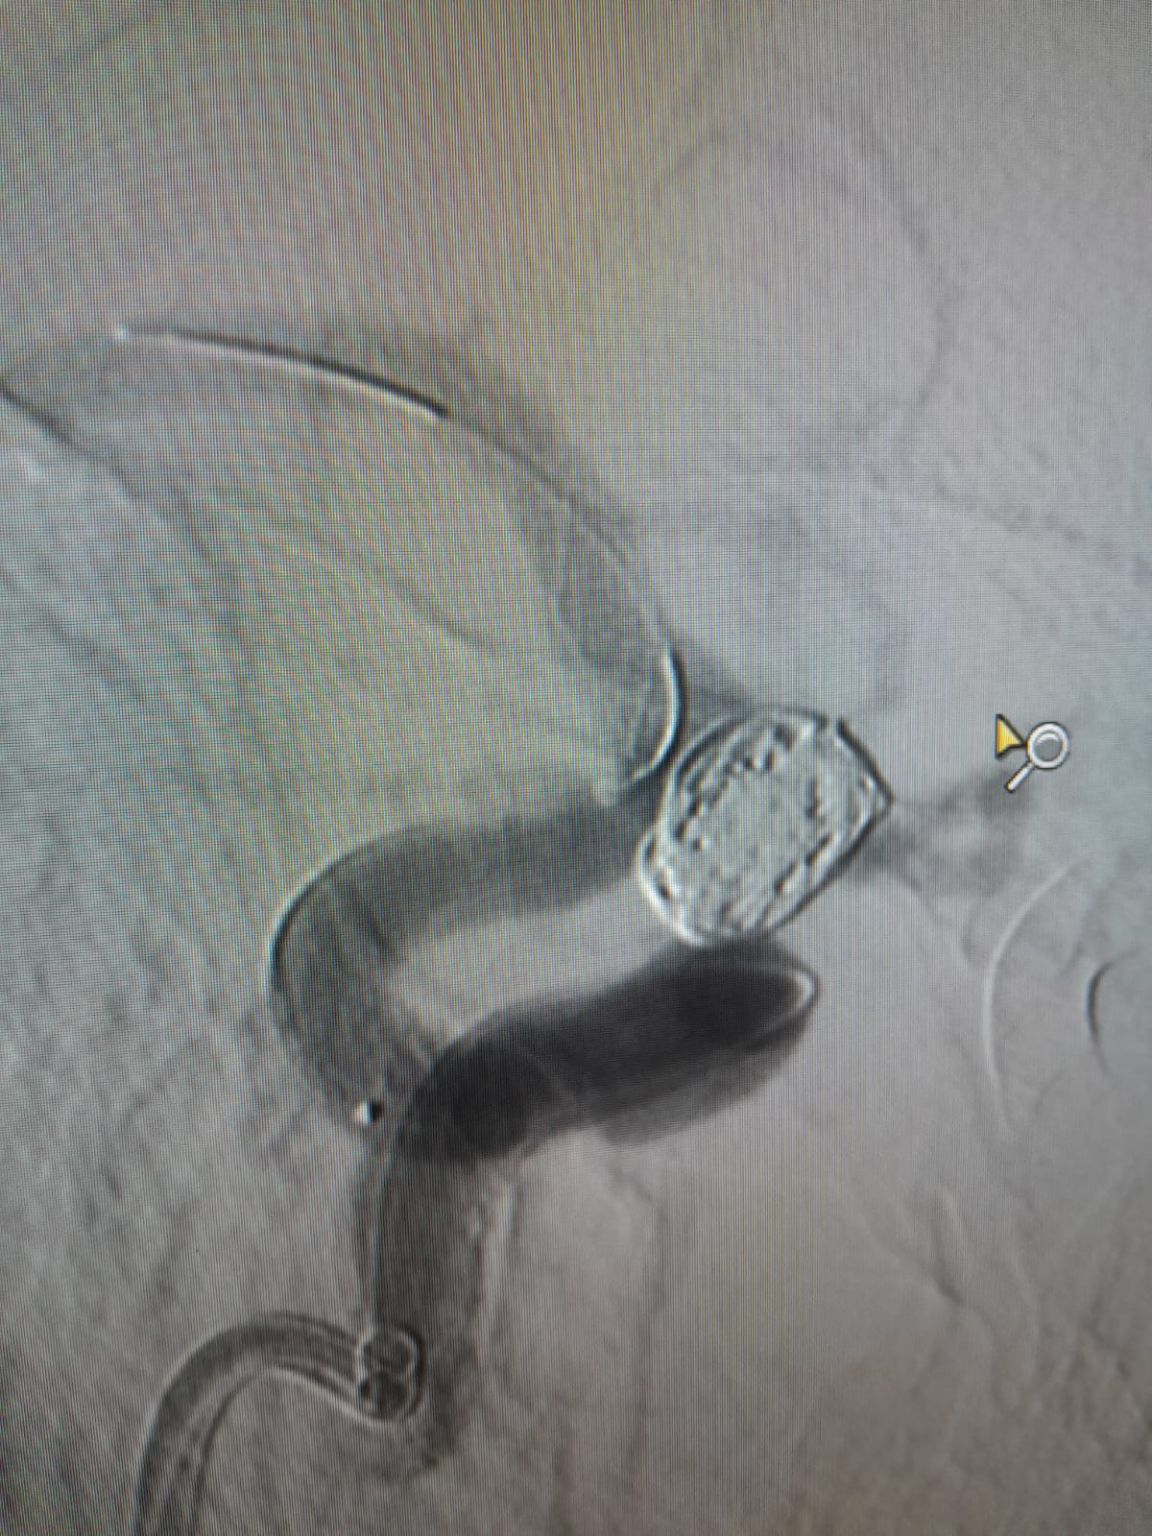

La procedura è stata eseguita con successo presso la Clinica Centenario dal Dr. Rivera, con il supporto del loro team clinico. L'accesso vascolare è stato stabilito tramite puntura dell'arteria femorale. Un microwire è stato accuratamente navigato verso il sito di destinazione, seguito dal regolare avanzamento del Frepass®Microcatetere monouso (TJMC18 Plus). Dopo una precisa misurazione dell'aneurisma, un Nuva®Flow Diverter (TJED-D-4.5-14) è stato selezionato e distribuito con successo sul collo dell'aneurisma.

La procedura è stata completata senza complicazioni, e la Nuva®Il dispositivo ha dimostrato un eccellente effetto di deviazione del flusso e dell'apposizione della parete. Il team clinico ha altamente riconosciuto la gestione e le prestazioni del dispositivo.